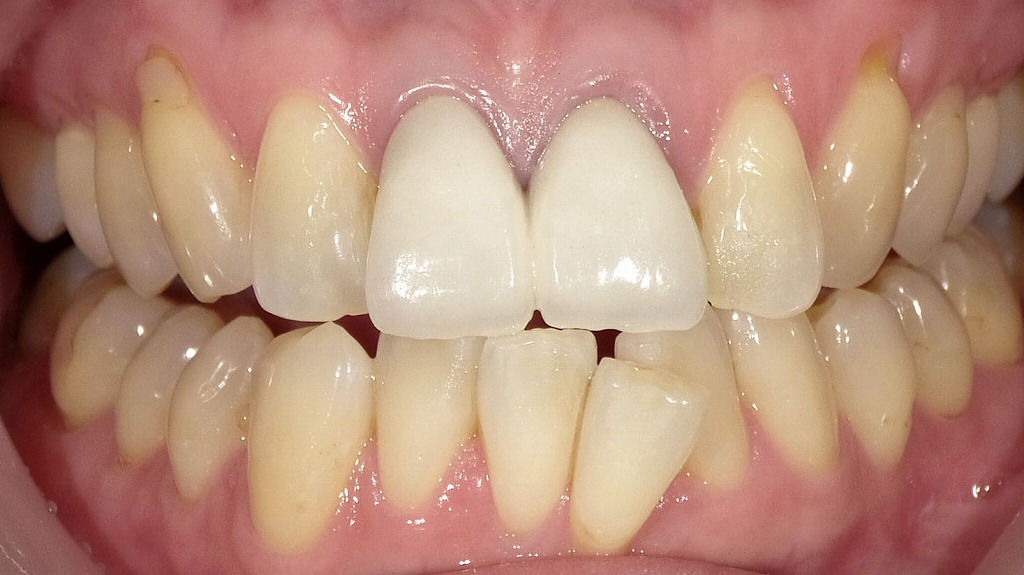

前歯が折れた症例とメタルボンドによる治療後の変化

前歯が折れて歯質を大きく失っていた症例に対し、メタルボンドクラウンを用いて機能と審美性の回復を行いました。内側に金属を使用することで強度を確保し、外側はセラミックで覆うため、前歯でも自然な見た目が得られます。咬合の安定と長期的な耐久性を重視した治療結果です